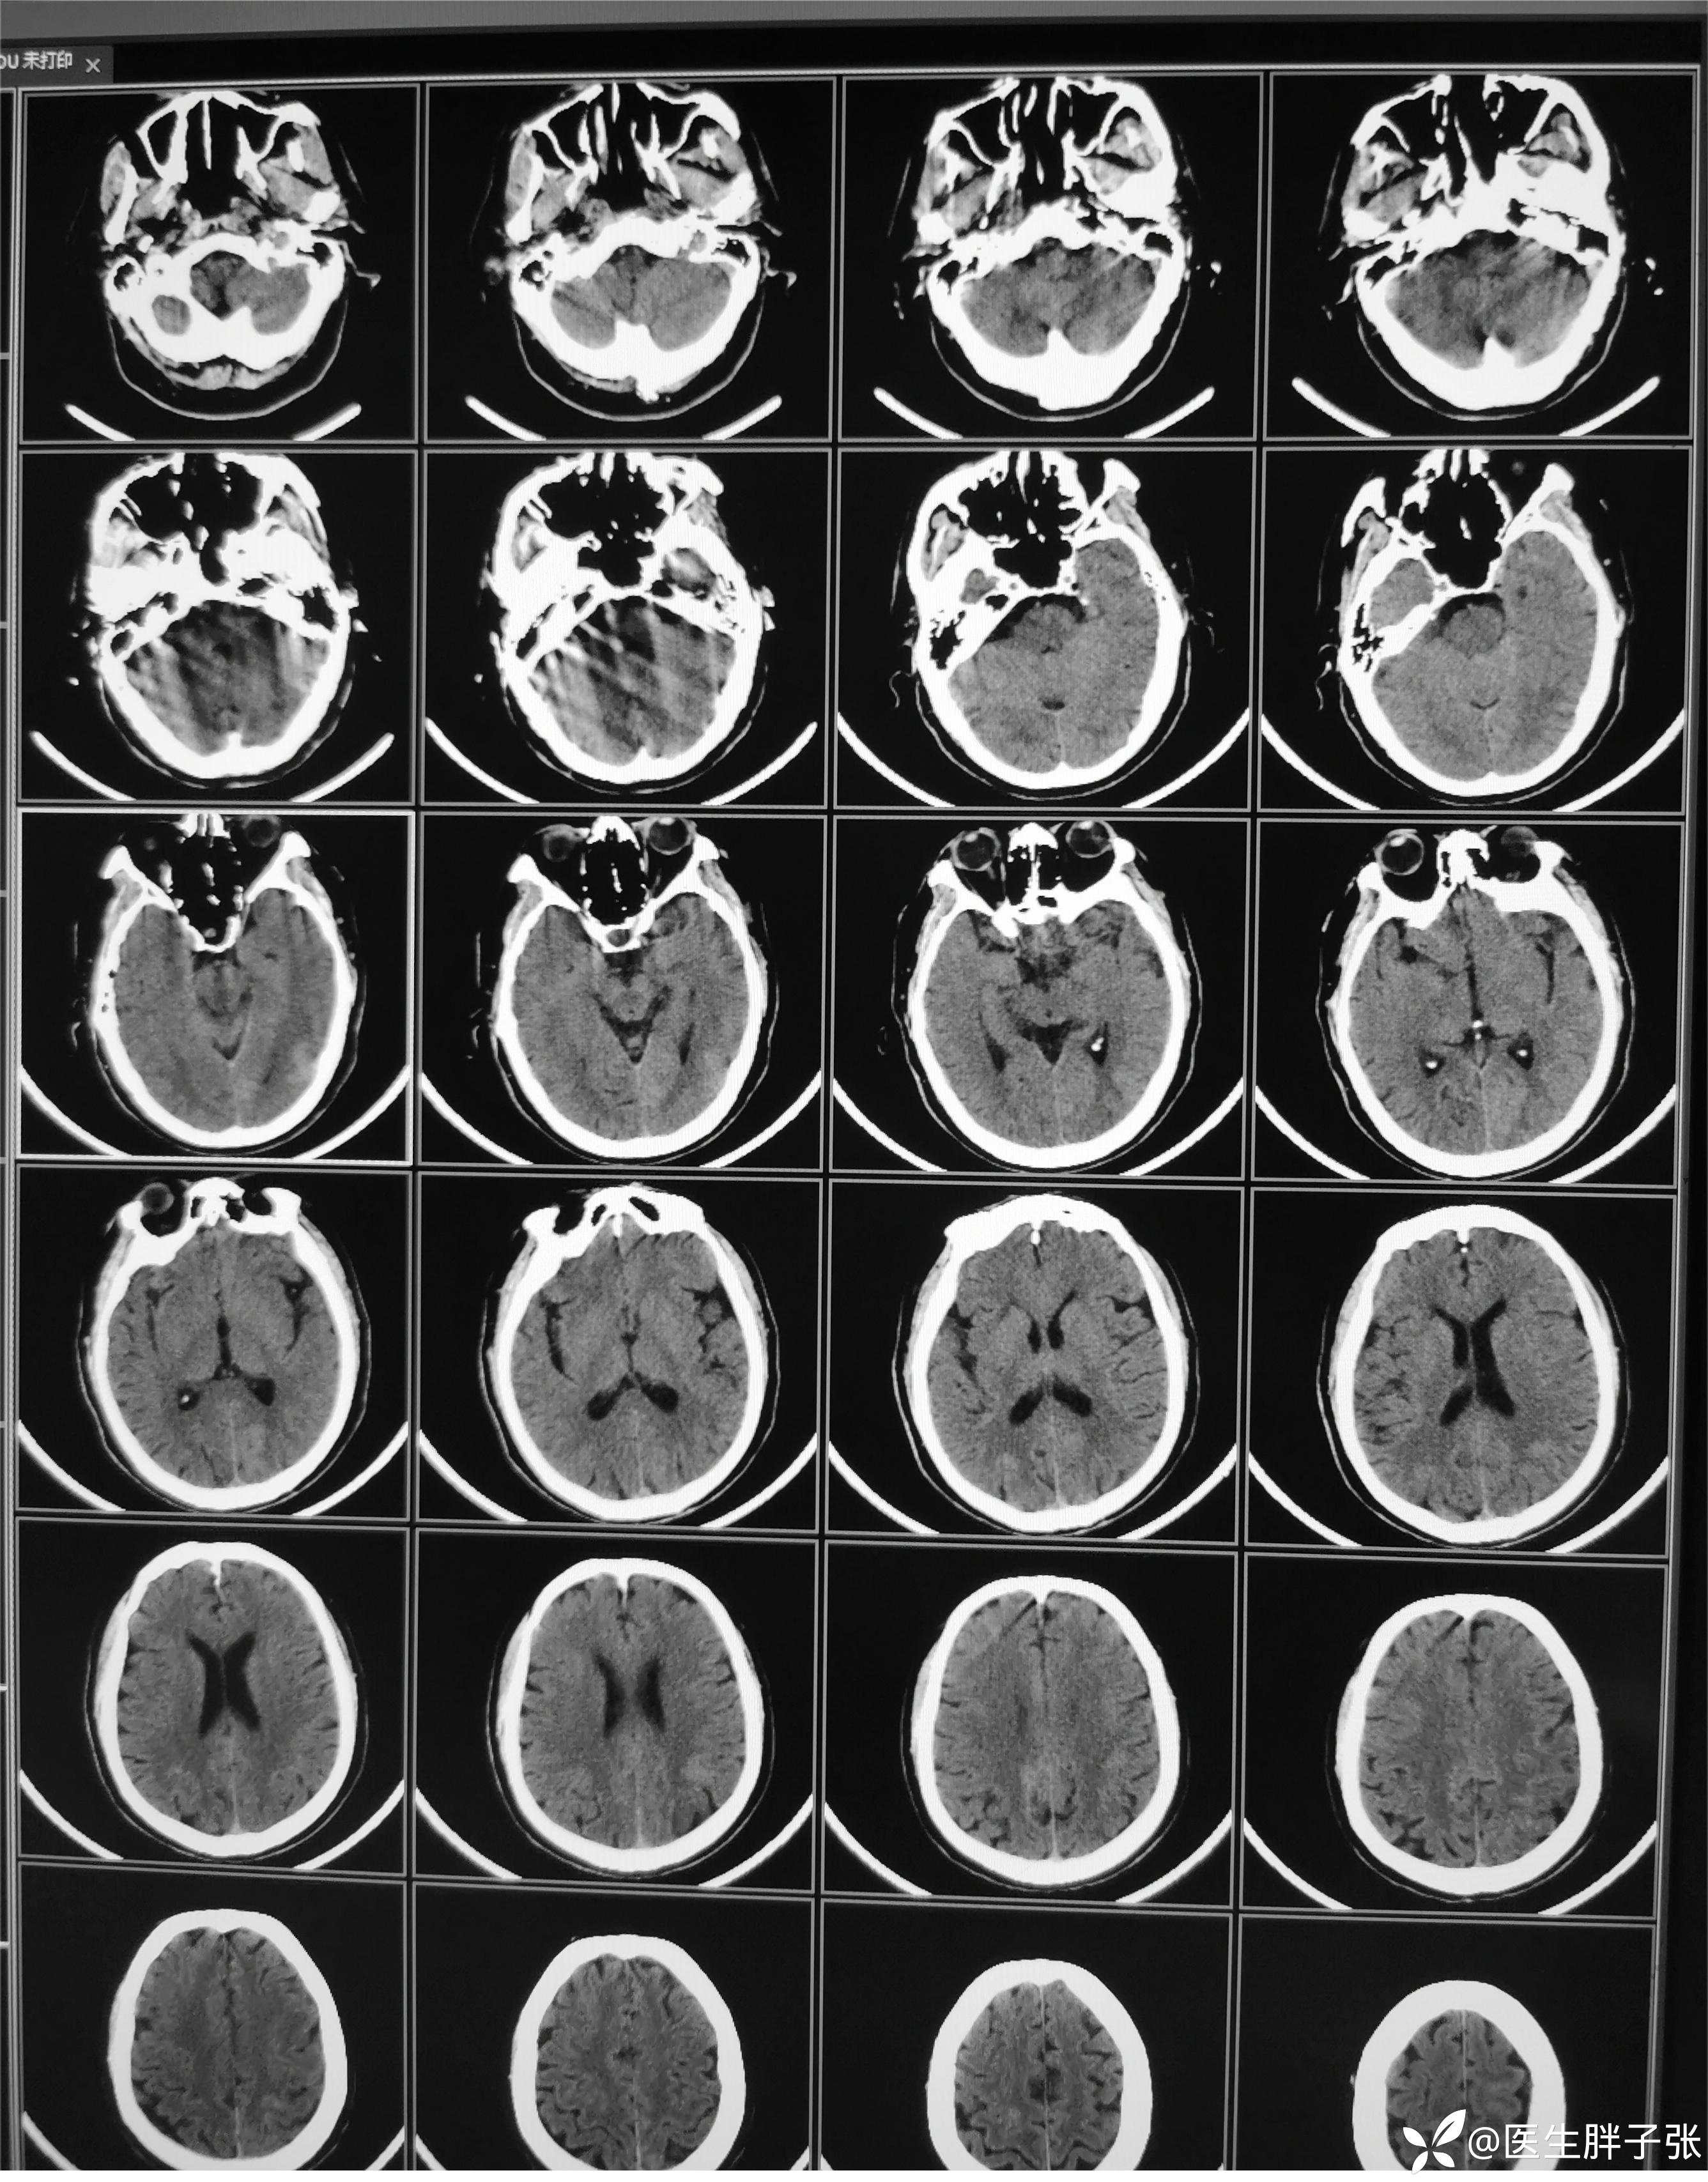

颅脑MR回报左侧顶叶新近梗死灶;多发腔隙性脑梗死及缺血灶;MRA未见异常。

再次查看核磁,考虑患者左侧顶枕叶及右侧枕叶脑组织存在混杂信号。

复查头颅CT,值班医生认为仍存在脑肿胀